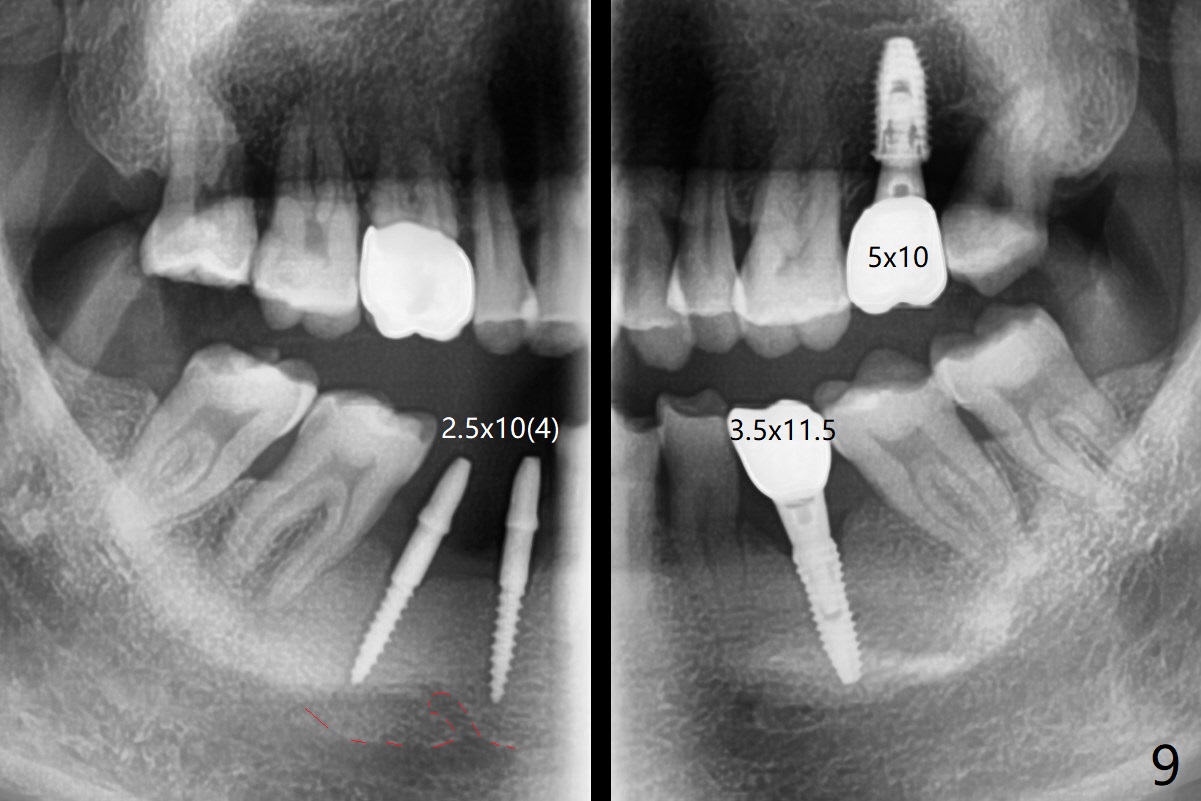

After initial osteotomy using 2.2 mm drill for 10 and 11.5 mm at #29 and 30, respectively, the guide is removed for re-insertion of drills and PA (Fig.1). The osteotomy at #29 is found lingually and in the nonkeratinized gingiva with mild laceration (wish incision to be made before osteotomy); the osteotomy is established a little lingual at #29 (Fig.2) and more or less in the middle of the narrow ridge and #30 (Fig.3). Lindamann bur is used to move #29 osteotomy buccally. A 1.5 mm drill is used to increase the depth free hand before placement of 2.5x10(4) mm 1-piece implants (Fig.4). After adjustment of the implant depth (Fig.5), CT is retaken, which shows proper implant placement (Fig.6,7). Probably due to good oral hygiene, the gingiva around the implants appears to be keratinized 4 months postop (Fig.8). After abutment preparation for margin and parallelism, impression is taken (Fig.9). When the permanent crowns are temporarily cemented, the large gingival embrasure is noted (Fig.10,11). The latter could be reduced by modifying the provisional in the healing stage. In fact the crown at #29 dislodges 2 days post cementation because lingual (Fig.12) and distal (Fig.13) placement. A surgical stent should have been fabricated from RPD for free hand placement!